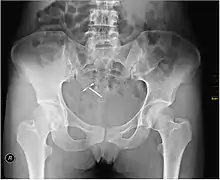

Intrauterine device

An intrauterine device (IUD), also known as intrauterine contraceptive device (IUCD or ICD) or coil,[3] is a small, often T-shaped birth control device that is inserted into the uterus to prevent pregnancy. IUDs are one form of long-acting reversible birth control (LARC).[4] One study found that female family planning providers choose LARC methods more often (41.7%) than the general public (12.1%).[5] Among birth control methods, IUDs, along with other contraceptive implants, result in the greatest satisfaction among users.[6]